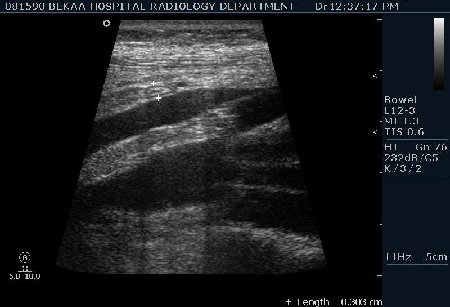

Диагностика острого аппендицита по УЗИ: очень актуальная тема; УЗ аппараты практически есть во всех клиниках; метод доступный и не сложный; главное владеть правильной техникой. Не буду загружать лишней теорией и разными ссылками; поделюсь практическим опытом. У меня линейный датчик 3-12 мегагерц с плавающей частотой; аппарат Филипс HD 11, всегда включаю соно-КТ (9800 цифровых каналов) и гармонику когда смотрю кишечник. Нормальный аппендикс видеть можно; но вопрос зачем??? Как правило, если при наличии достаточного опыта аппендикс не виден; значит скорей всего аппендицита нет. Когда "идешь" на аппендицит то главное по началу набраться терпения и......хорошая компрессия! По началу надо минут 10-15; потом когда появится достаточный опыт; за 2-5 минут можно справится и получить отличную визуализацию. Мочевой пузырь лучше опорожнить; часто он приподнимают тонкий кишечник и может закрыть "окно" через которое будет видно апендикс. Сначала находим слепую кишку потом находим илео-цекальное соединение;

после начинаем производить хорошую компрессию датчиком попрося пациента сообщить в какой точке боль наиболее выражена; медленными движениями датчика сканируем область наибольших болевых ощущений и как правило находим утолщенный отросток. Лучше начинать с поперечной визуализации и идти к верхушке аппендикса что бы убедится что это аппендикс и он заканчивается, а не тонкая кишка (которая если и закончится то только переходя в слепую); потом надо аккуратно развернуть продольно датчик и посмотреть от верхушки аппендикса к слепой. Норма диаметра: 3-4 мм; 5-6 мм под вопросом (клиника решает; но я в катаральный аппендицит не верю); 7-8 мм и больше, не компремируемый (фиксированный отросток)-острый аппендицит! Помимо наличие утолщенного аппендикса; признака "бычьего глаза" (bull-eye sign) при поперечном сканировании; надо обращать внимание на присуствие аппендоколитов в просвете; деструкцию стенки и свободной жидкости в зоне интереса.